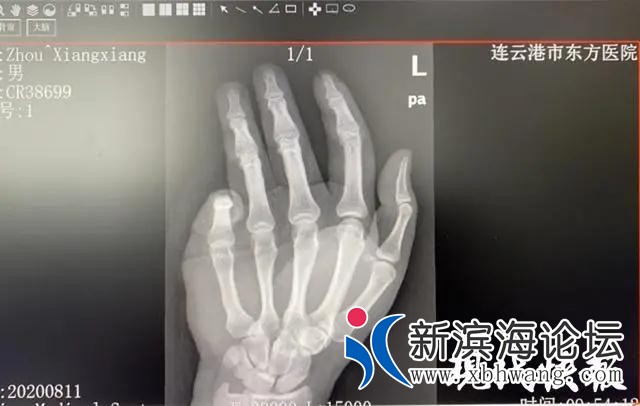

该院手足外科副主任董波接诊后,看到周先生的左手鲜血淋淋,小指远节部分缺失,整个小指皮肤苍白,董波立马将周先生的离体小指用冰块保存好,随即开始帮助周先生清理包扎伤口,并立即为其开通绿色通道,办理入院手续。通过 X 光片检查董波发现,周先生小指末端已经骨折。" 他的小指最后一截已经完全断离,而且指骨骨折,当时的情况,越快手术再植成功率越高。" 董波说道。